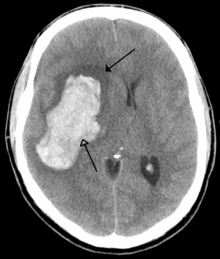

CT scan of an intraparenchymal bleed (bottom arrow) with surrounding edema (top arrow)

There are two main types of hemorrhagic stroke:[28][29]

• Intracerebral hemorrhage, which is basically bleeding within the brain itself (when an artery in the brain bursts, flooding the surrounding tissue with blood), due to either intraparenchymal hemorrhage (bleeding within the brain tissue) or intraventricular hemorrhage (bleeding within the brain's ventricular system).

• Subarachnoid hemorrhage, which is basically bleeding that occurs outside of the brain tissue but still within the skull, and precisely between the arachnoid mater and pia mater (the delicate innermost layer of the three layers of the meninges that surround the brain).